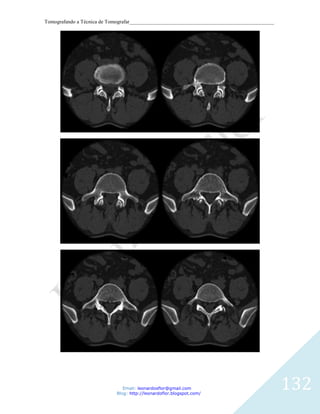

CORTES AXIAIS DA MASTOIDE